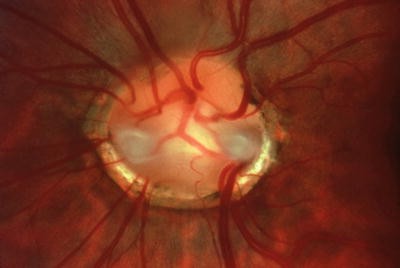

Moyamoya optic disc. (a) In the morning glory disc anomaly, absence of central retinal vasculature gives rise to compensatory collateralization of chorioretinal anastomoses (cilioretinal vessels) to also impart a “moyamoya” bypass system that is ophthalmoscopically visible within the distal optic nerve. (b) Color Doppler ultrasonography demonstrates the absence of vasculature within the central optic nerve. (From Brodsky MC and Parsa CF [64], with permission.)